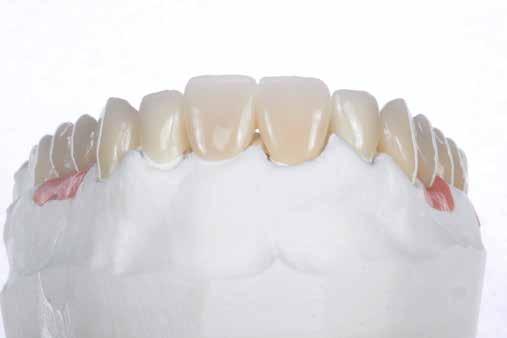

A front régióban alkalmazott minimál invazív multidiszciplináris megközelítés eredményeként jelentős mértékben tudtuk javítani a páciens esztétikai megjelenését. A beavatkozások során japán washi papír felhasználásával történő belső fogfehérítést, valamint háromdimenziós nyomtatással készült sebészeti sablon által vezetett ínyplasztikát végeztünk, majd az esztétikai zónában lévő fogakat – köztük egy elszíneződött nagymetsző fogat – ultravékony földpátkerámia héjakkal láttuk el.

A páciens elsősorban a mosolyának megjelenésén szeretett volna javítani. Egy előzetes állapotfelmérést követően az elszíneződött fog belső fehérítését, ínyplasztikát, valamint a felső front- és első kisőrlőfogak esztétikai célú helyreállítását javasoltuk. A belső fogfehérítés során nátrium-perborát és 30%-os hidrogén-peroxid keverékével átitatott washi papírt alkalmaztunk. Az anyag pulpakamrába történő helyezését követően az üreget üvegionomer cementtel zártuk. A fogfehérítés befejezését követően 3D nyomtatott sebészi sablont készítettünk, majd a felső front régióban megfigyelhető lágyrészek lefutását ezen sablon segítségével korrigáltuk. A sebészi beavatkozást követően 6 hónappal ultravékony földpátkerámia héjakat készítettünk.

A rendelésünkön jelentkező 40 éves nőbeteg a mosolyának esztétikai megjelenésén szeretett volna javítani (1. ábra)

A vizsgálat során a jobb felső első kisőrlőfog (1,4) és a bal felső első kisőrlőfog (2.4), valamint a köztük elhelyezkedő fogak kifejezett mértékű kopását észleltük (14-24). Ezen felül a felső metszőfogak (1.2–2.2) élei egyenetlen lefutással rendelkeztek, és a jobb felső nagymetszőfog (11) – amelyet korábban gyökérkezeltek és kompozit töméssel láttak el –jelentős színbeli eltérést mutatott. Az 1.4-es és 2.4-es fo-

A belső fogfehérítés utáni állapot.

gak között mért tasakmélység mértéke sehol sem haladta meg a 3 mm-t. A páciens számára belső fogfehérítést, ínyplasztikát és kerámia héjak készítését javasoltuk. A páciens a felajánlott kezelési tervet elfogadta. Első lépésként az 1.1es fog belső fogfehérítését terveztük, mivel a későbbiekben ezt a fogat is kerámia héjjal akartuk ellátni.

A páciens elégedett volt a végleges restaurátumok színével, formájával és méretével. A kezelés végeredménye kielégítette az esztétikai elvárásait (9. ábra). A frissen átadott restaurátumok épségének megőrzése érdekében a páciens számára éjszakai fogvédősínt készítettünk. A páciensünk a négyéves kontrollvizsgálat során is nagyon elégedett volt a kezelés eredményével. A korábban meglévő fekete háromszögek eltűnésének különösképpen örült (9. és 10. ábrák)

Jelen esettanulmányban három meglévő technika kombinálását és továbbfejlesztését mutattuk be: washi papír használatával történő belső fogfehérítést, nyomtatott sebészi sablon által vezetett ínyplasztikát, és a fogakra ultravékony földpátkerámia héjakkal történő ellátását. E bonyolult eset kezelése során – minimálinvazív megközelítés mellett – kiemelkedő esztétikai eredményt sikerült elérni.

Az alapos tervezést követően végzett restauratív beavatkozások során sikeresen kombináltuk a washi papírral végzett belső fogfehérítést, a 3D nyomtatott sebészeti sablonnal és elektrokauterrel végzett ínyplasztikát, továbbá az ultravékony földpátkerámia héjakkal történő ellátást. A kezelési terv követésével el lehetett érni a kívánt esztétikai eredményeket, amelyek már 4 éve stabilnak bizonyultak.